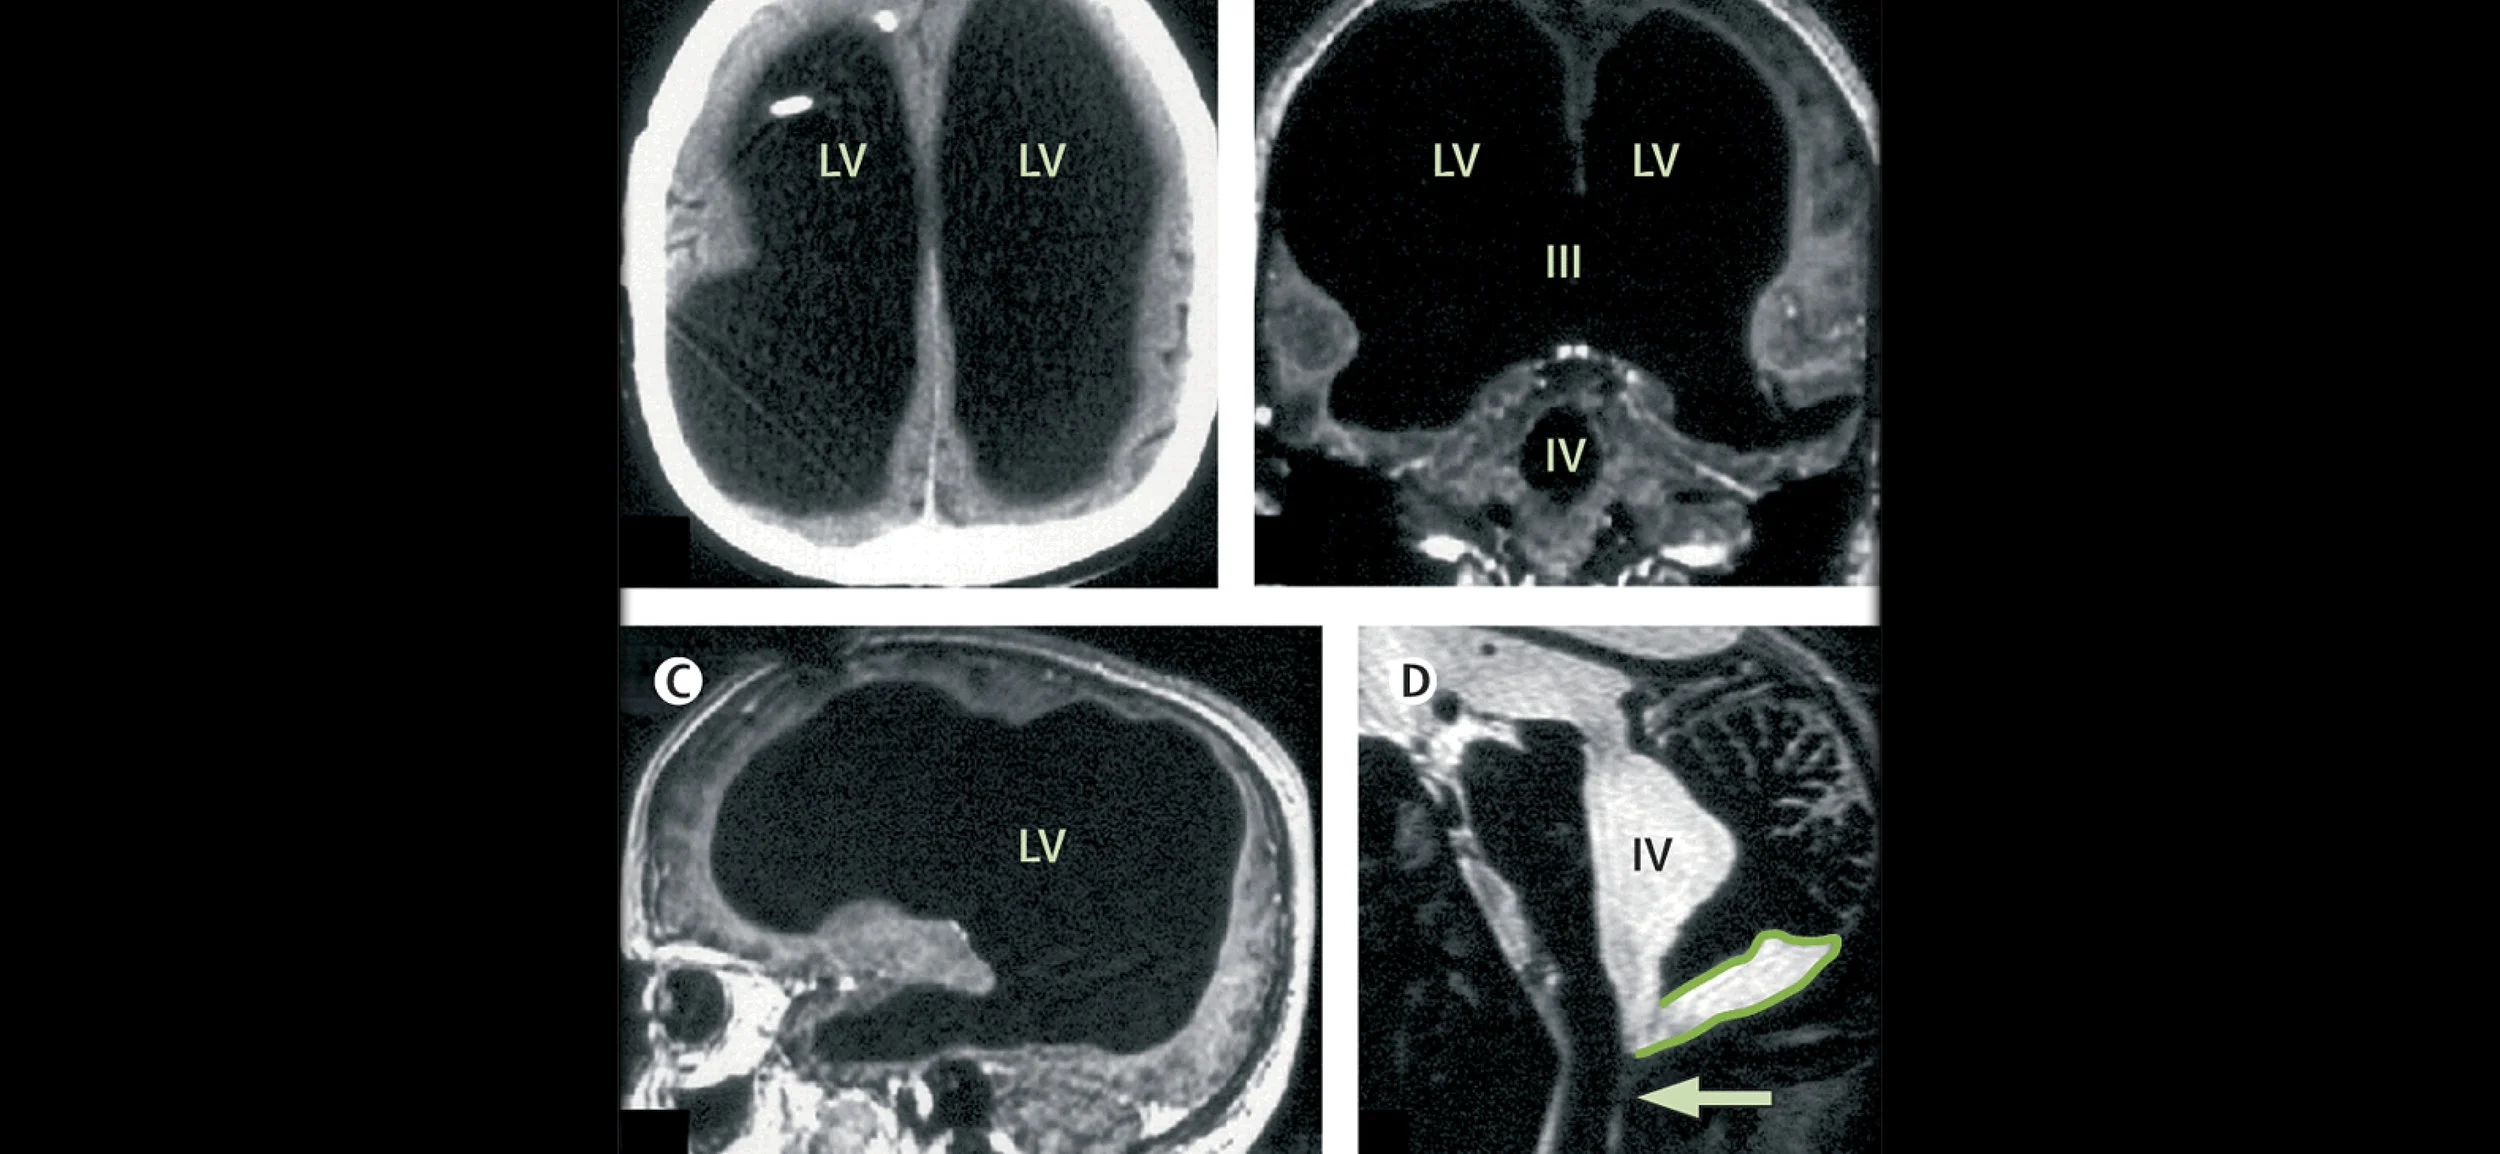

Not much is definitively proven about consciousness, the awareness of one’s existence and surroundings, other than that it’s somehow linked to the brain. But theories as to how, exactly, grey matter generates consciousness are challenged when a fully conscious man is found to be missing most of his brain. Several years ago, a 44-year-old Frenchman went to the hospital complaining of mild weakness in his left leg. It was discovered then that his skull was filled largely by fluid, leaving just a thin perimeter of actual brain tissue. And yet the man was a married father of two and a civil servant with an IQ of 75, below-average in his intelligence but not mentally disabled. Doctors believe the man’s brain slowly eroded over 30 years due to a buildup of fluid in the brain’s ventricles, a condition known as “hydrocephalus.” He was treated with a shunt, which drains the fluid into the bloodstream, when he was an infant. But it was removed when he was 14. Over the following decades, the fluid accumulated, leaving less and less space for his brain. While this may seem medically miraculous, it also poses a major challenge for cognitive psychologists, says Axel Cleeremans of the Université Libre de Bruxelles. “Any theory of consciousness has to be able to explain why a person like that, who’s missing 90% of his neurons, still exhibits normal behavior,” says Cleeremans. A theory of consciousness that depends on “specific neuroanatomical features” (the physical make-up of the brain) would have trouble explaining such cases. In theory, the frontal, parietal, temporal, and occipital lobes in the brain control motion, sensibility, language, vision, audition, and emotional and cognitive functions. But these regions were all reduced in the Frenchman. He did not, however, suffer significant mental effects, suggesting that, if an injury occurs slowly over time, the brain can adapt to survive despite major damage in these regions. Cleeremans, who gave a lecture on the subject at the Association for the Scientific Study of Consciousness conference in Buenos Aires, believes that the seeming plasticity of the brain is key to understanding how consciousness operates. He believes that the brain learns to be conscious. As such, few specific neural features are necessary for consciousness, since areas of the brain can adapt and develop consciousness. “Consciousness is the brain’s non-conceptual theory about itself, gained through experience—that is learning, interacting with itself, the world, and with other people,” he says. In his thesis, Cleeremans argues that in order to be aware, it’s necessary not simply to know information, but to know that one knows information. Cleeremans claims that the brain is continually and unconsciously learning to re-describe its own activity to itself, and these descriptions form the basis of conscious experience. Ultimately, Cleeremans believes that consciousness is “the brain’s theory about itself.” And so, while the Frenchman may have had a tiny brain, it was still apparently able to generate a theory about itself and is “a striking case of how the brain learns to adapt.”